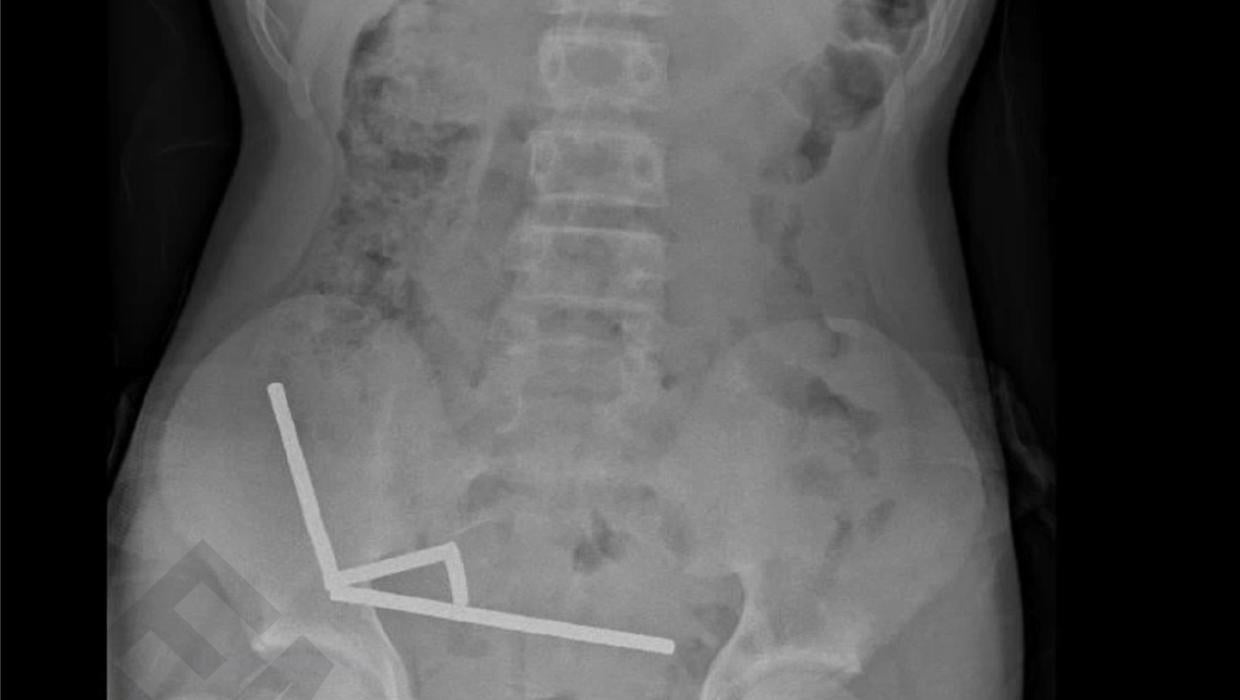

A thirteen-year-old boy required emergency surgery after swallowing a significant number of magnets. The incident occurred in New Zealand, where the child underwent a complex procedure at Tauranga Hospital to address the life-threatening situation.

Doctors reported that the boy had ingested up to 100 magnets, leading to serious complications. The emergency surgery involved the removal of a portion of his bowel due to the severe internal damage caused by the magnets. Medical professionals emphasized the dangers of such ingestible items, particularly for young children who may not fully understand their risks.

The boy’s condition was critical upon arrival at the hospital, necessitating immediate action from the surgical team. According to a statement from the hospital, the surgery was classified as “major,” highlighting the seriousness of the situation.